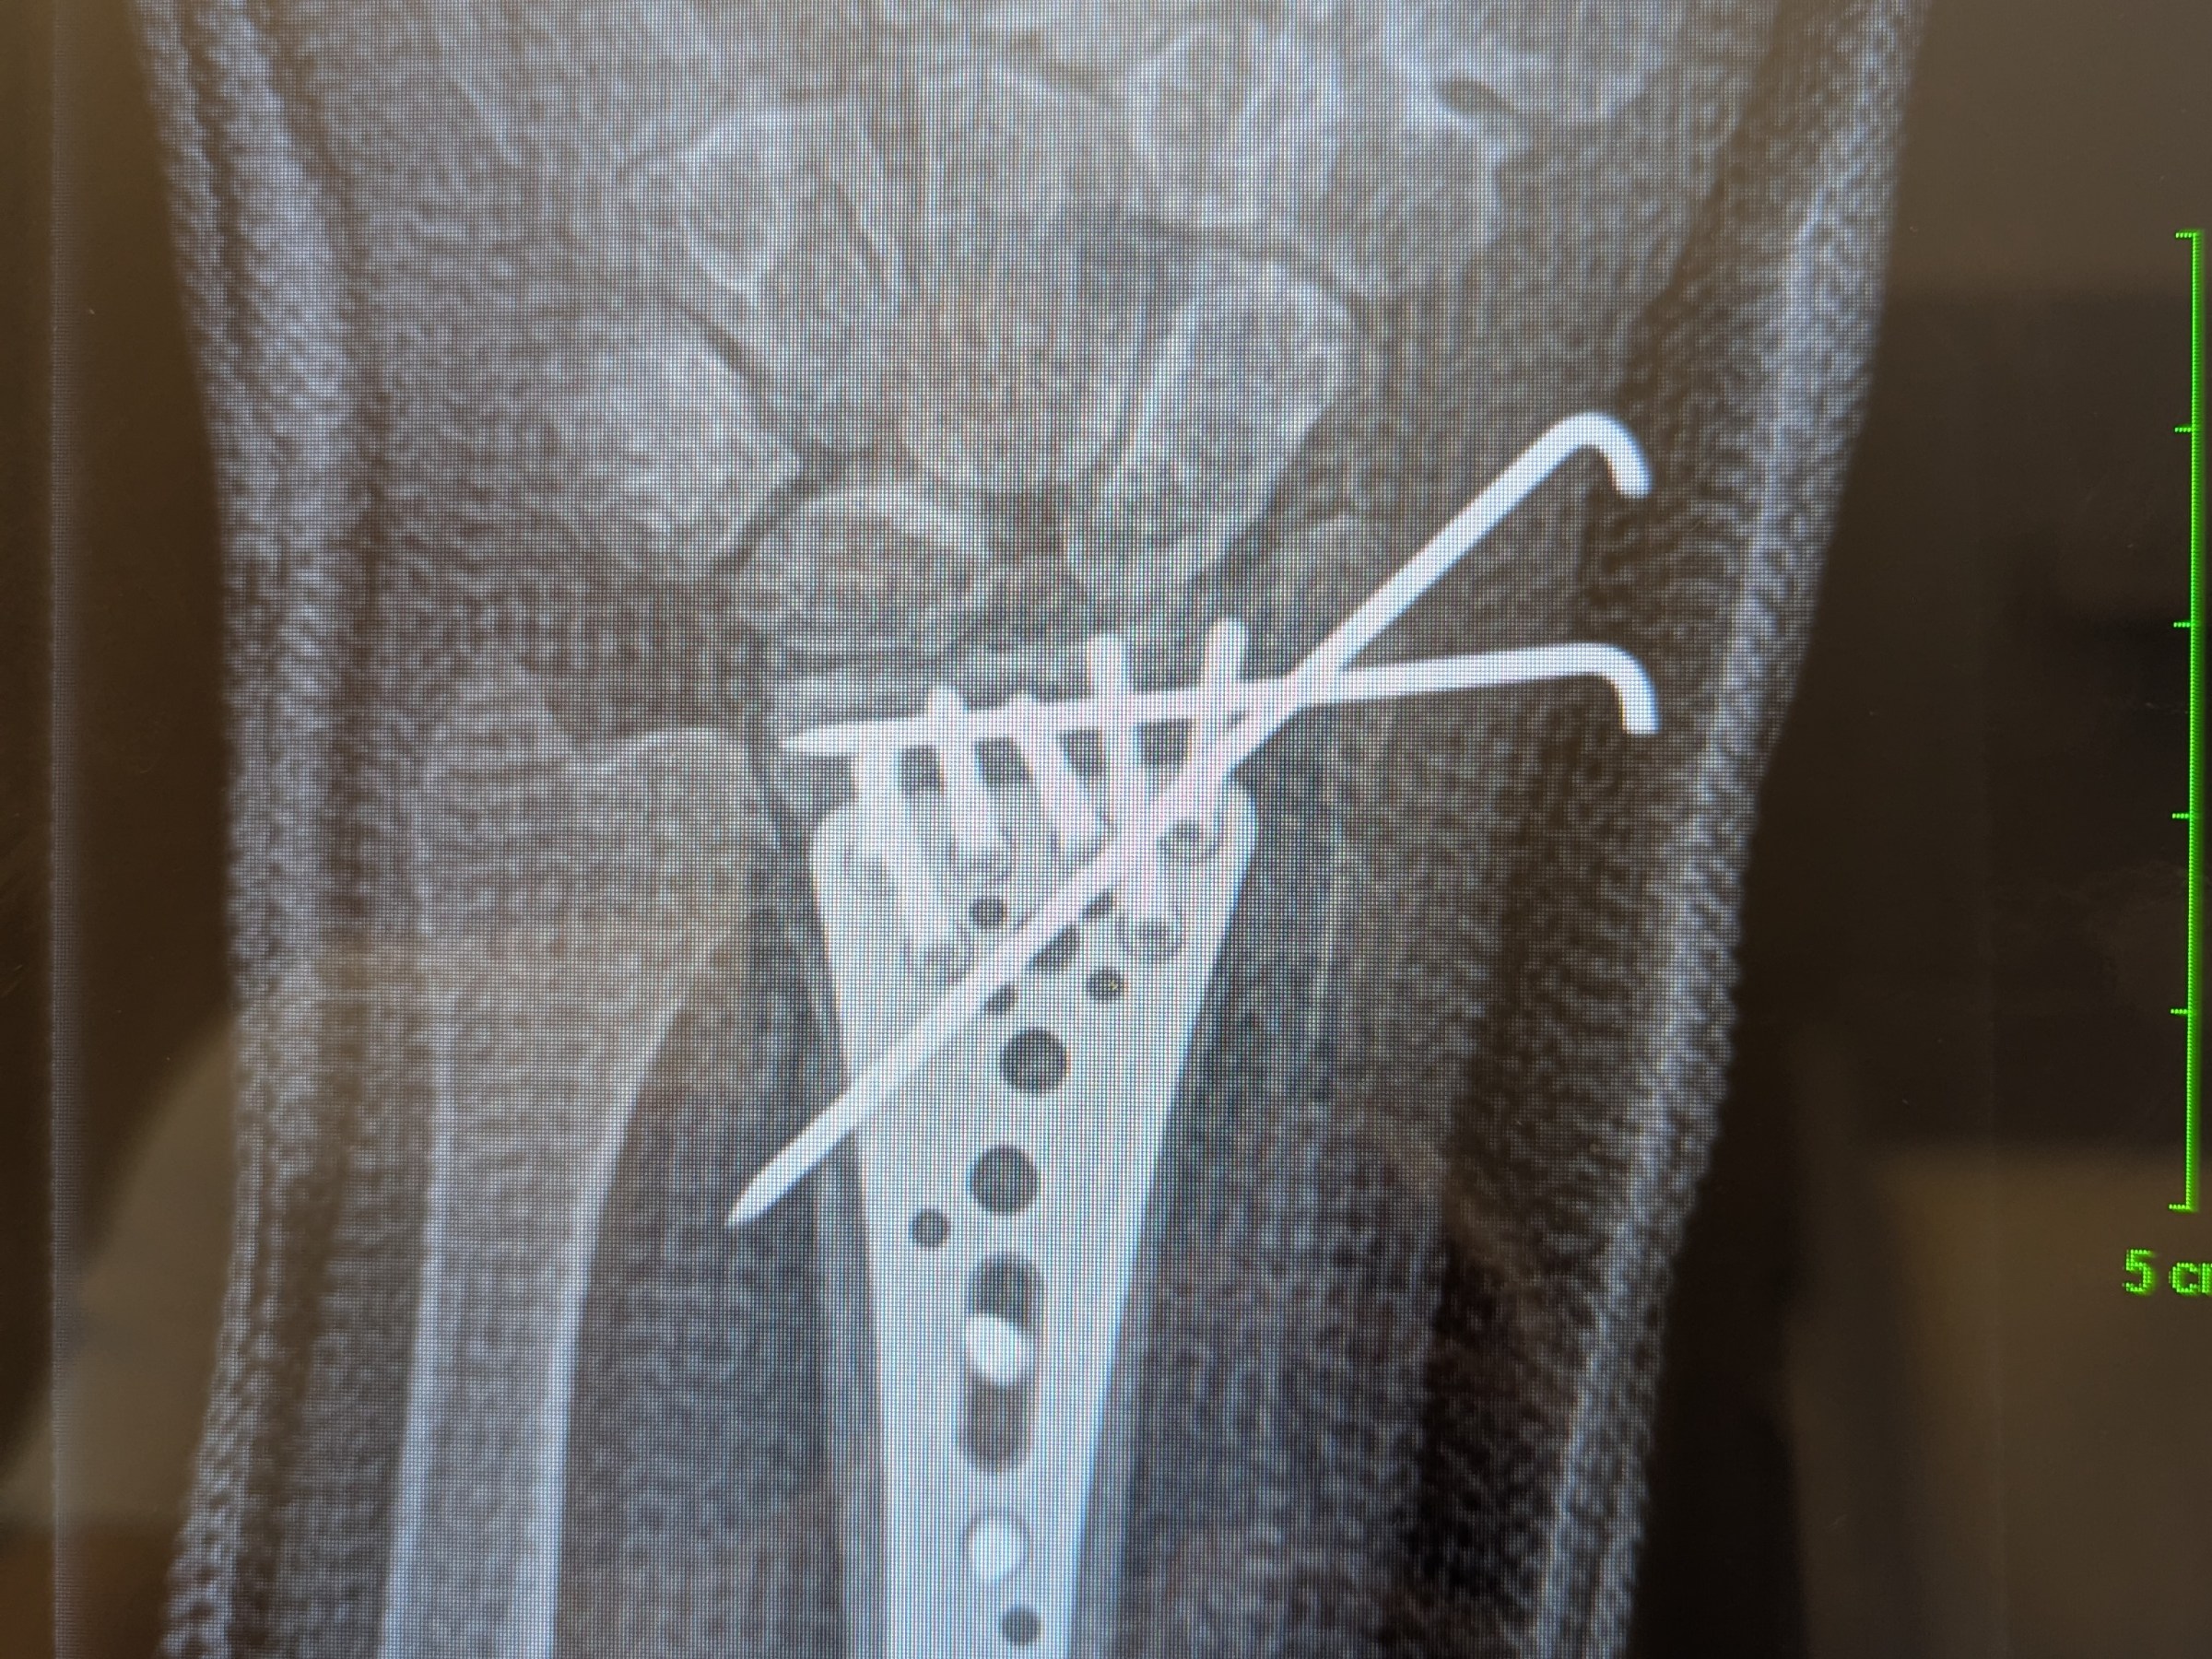

Erst Knie, dann Hand, jetzt Hustenqual, dieses Jahr kann mich mal … … aber sowas von! 🙄🙄🙄